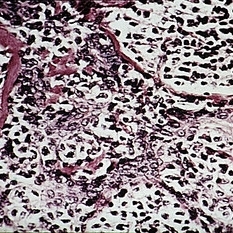

Burkitt's lymphoma. Undifferentiated, diffuse lymphosarcoma shows scattered macrophages engulfing nuclear debris, giving a "starry-sky" appearance to the tumor (H&E x252).

Condition/keywords: Burkitt's lymphoma, lymphosarcoma